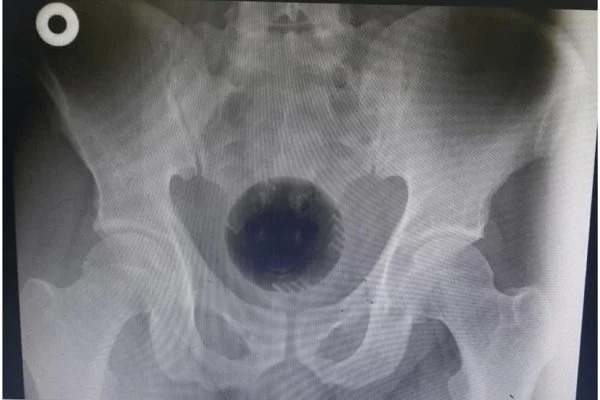

Um homem de 51 anos da Jordânia passou por uma cirurgia de emergência para retirar uma bola de plástico de 7 centímetros de diâmetro, equivalente ao tamanho de uma bola de tênis, que ficou presa no reto. Relatado no International Journal of Surgery Case Reports, o caso foi noticiado pelo jornal The Sun nesta terça-feira, 13.

A bola, que fazia parte de um aspirador de pó, ficou presa na pélvis do paciente. Ele contou aos médicos que introduziu o objeto no próprio corpo com a esperança de solucionar um problema de hemorroidas. A equipe relatou, entretanto, não ter encontrado evidências desta condição de saúde.